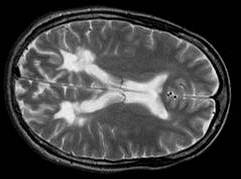

What type of image is it? MRI scans (T1 or T2 weighted)

Which plane the image is in? axial, sagittal or coronal (see

pictures below)

Axial scan |